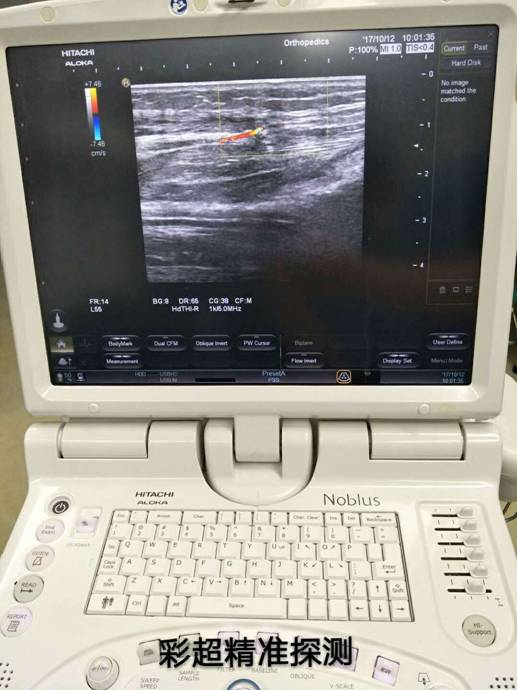

骨科根據(jù)患者骨折情況分別施行骨折復(fù)位+內(nèi)(外)固定術(shù),然后由燒傷整形科根據(jù)患者皮膚軟組織缺損情況,制定小腿穿支皮瓣轉(zhuǎn)移修復(fù)創(chuàng)面方案。為保證手術(shù)成功率,燒傷整形科會(huì)同超聲科由黃道遠(yuǎn)主任于術(shù)前利用彩超精準(zhǔn)的探測(cè)小腿術(shù)區(qū)的各個(gè)動(dòng)脈穿刺,并逐一標(biāo)記,再由燒傷整形科手術(shù)團(tuán)隊(duì)根據(jù)動(dòng)脈穿支的分布情況設(shè)計(jì)皮瓣,施行小腿穿支皮瓣轉(zhuǎn)移修復(fù)術(shù)。

由于采用了彩超定位技術(shù),使得皮瓣設(shè)計(jì)方案更合理,手術(shù)操作更精準(zhǔn),手術(shù)耗時(shí)更少,更因?yàn)楸Wo(hù)好了血管,術(shù)后皮瓣腫脹,存活均較以往有明顯改善,手術(shù)效果得到極大保障,患者滿意度大大提高。